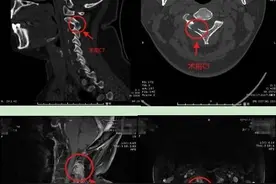

脊柱嗜酸性肉芽肿